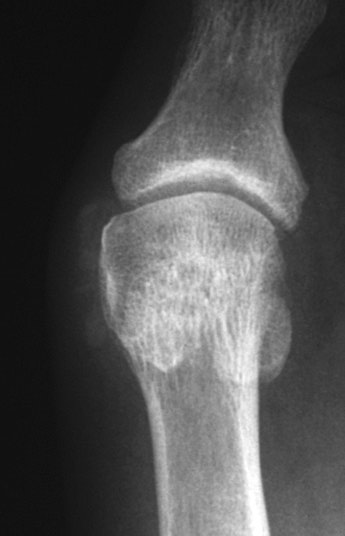

The first metatarsal head and sesamoids also become malaligned with each other.

Sesamoid:

Short axis view of first metatarsophalangeal joint. The two large sesamoid bones are present beneath the first metatarsophalangeal joint within the tendons of the flexor hallucis brevis. With the development of hallux valgus, the 1st metatarsal head migrates medially and dorsally. The fibular sesamoid frequently rotates slightly dorsally, and is seen on the AP film in profile.